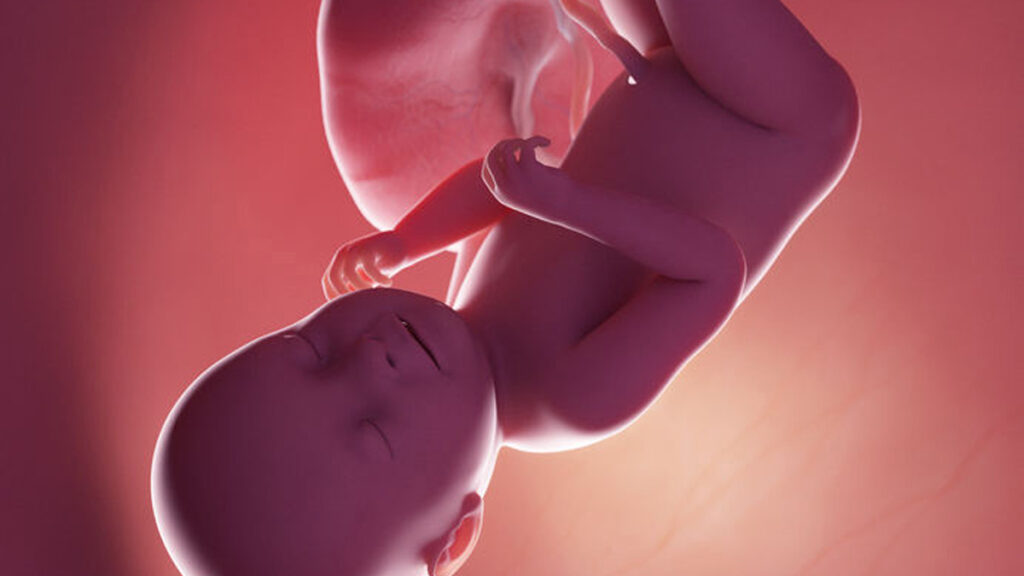

Als er verder geen complicaties zijn en je wilt het zelf ook, dan mag je vanaf deze week thuisbevallen. Je kindje is voldragen en kan veilig geboren worden. Het enige dat hij nog doet zolang hij nog bij je is, is een beetje groeien (20 tot 30 gram per dag), worden de hersenen en zenuwstelsel nog wat meer op elkaar afgestemd en wordt er meer babyvet gekweekt. Dat vetlaagje is goed voor zijn weerstand, zo heeft hij straks een beetje reserve.

Het wachten is dus nu begonnen op de eerste signalen van de bevalling. Hopelijk ligt hij inmiddels in de juiste richting, zodat ook hij er helemaal klaar voor is. In deze periode groeien zijn hoofdhaartjes ook nog verder, zodat dit steeds meer volume krijgt. Wie weet wat voor een bos haar hij straks heeft! Welke kleur zal het zijn? Spannend hoor!

In zijn longen zorgt een stofje ervoor dat de longblaasjes niet aan elkaar kleven als hij straks begint met ademhalen.